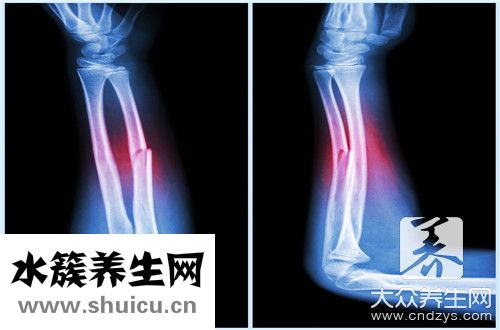

骨折一般没有年龄区分。 所有年龄段的人有时都是骨折。 上臂骨折是生活中普遍的情况。 一般情况下,一旦发生骨折,无论什么样的骨折,日常生活都会发生非常大的故障。 一旦发生骨折,必须马上就诊

上臂骨折直发夹板固定不动时,可把二块直发夹板各自置放到上臂的手心和掌骨间。可在患者患肢手心放一团棉絮,让伤者握紧掌侧直发夹板的一端,使肘关节稍向背屈,随后固定不动,再用三角巾将上臂悬架于胸口,再用三角巾将伤肢固定不动于膈肌。要留意外露手指尖,便于随时随地观查末梢神经血液循环系统,假如手指尖惨白,发冷,变紫,表明固定不动过紧,要松掉再次调节固定不动工作压力。

1、手臂骨折固定不动法:直发夹板置放骨折手臂两侧,骨折突显一部分要垫高,随后固定不动肘、肩两骨节,用三角巾将手臂曲屈悬胸口,再用三角巾将伤肢固定不动于伤者膈肌。

1、对单纯性合闭或挪动少的骨折,选用技巧复位,小直发夹板外固定不动。一般 用四块定形直发夹板。

2、对少年儿童或成年人轻微挪动上臂双骨折,技巧复位后屈肘90°,以管形熟石膏或熟石膏托超骨节固定不动。

3、对软组织损害较比较严重的开放性骨折,桡尺技术骨干好几处骨折,及其难以技巧复位或难以外固定不动的骨折,应割开复位,行厚钢板或髓内针或螺丝内固定不动。

4、对上臂软组织,肌肉血管损害比较严重发胀造成前臂骨肌肉筋膜室综合症务必初期割开缓解压力。